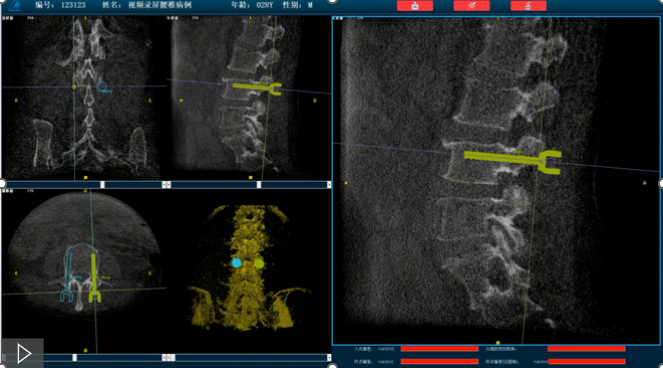

首先,需要明确的是机器人手术,机器人在术中还是做辅助性操作,术前基于三维C形臂等影像扫描得到骨骼结构的三维数据,机器人系统利用手术规划软件,引导医生进行可视化预手术规划(钉道规划、入钉角度),选择合适的螺钉规格、尺寸,辅助评估和及时调整手术路径规划设计,整台手术都是在主刀医生的把控下进行操作的?;魅讼低巢唤隹科祝一固嵘耸质醯陌踩?、机械臂的精准以及力传感识别、实时动态追踪等?;ぜ际?,增加了手术的准确性和安全性。

就以普爱医疗骨科机器人PL300B为例,骨科机器人可以保证亚毫米级精准度,例如在脊柱上植入椎弓根螺钉,传统手术需要暴露骨组织解剖结构,往往会有10-20cm的开口,而使用了手术机器人可以将开口转变为数个1-2cm的开口,出血量降低至95%以上,大大降低并发症的发生率,同时有益于病患的更快的术后恢复。